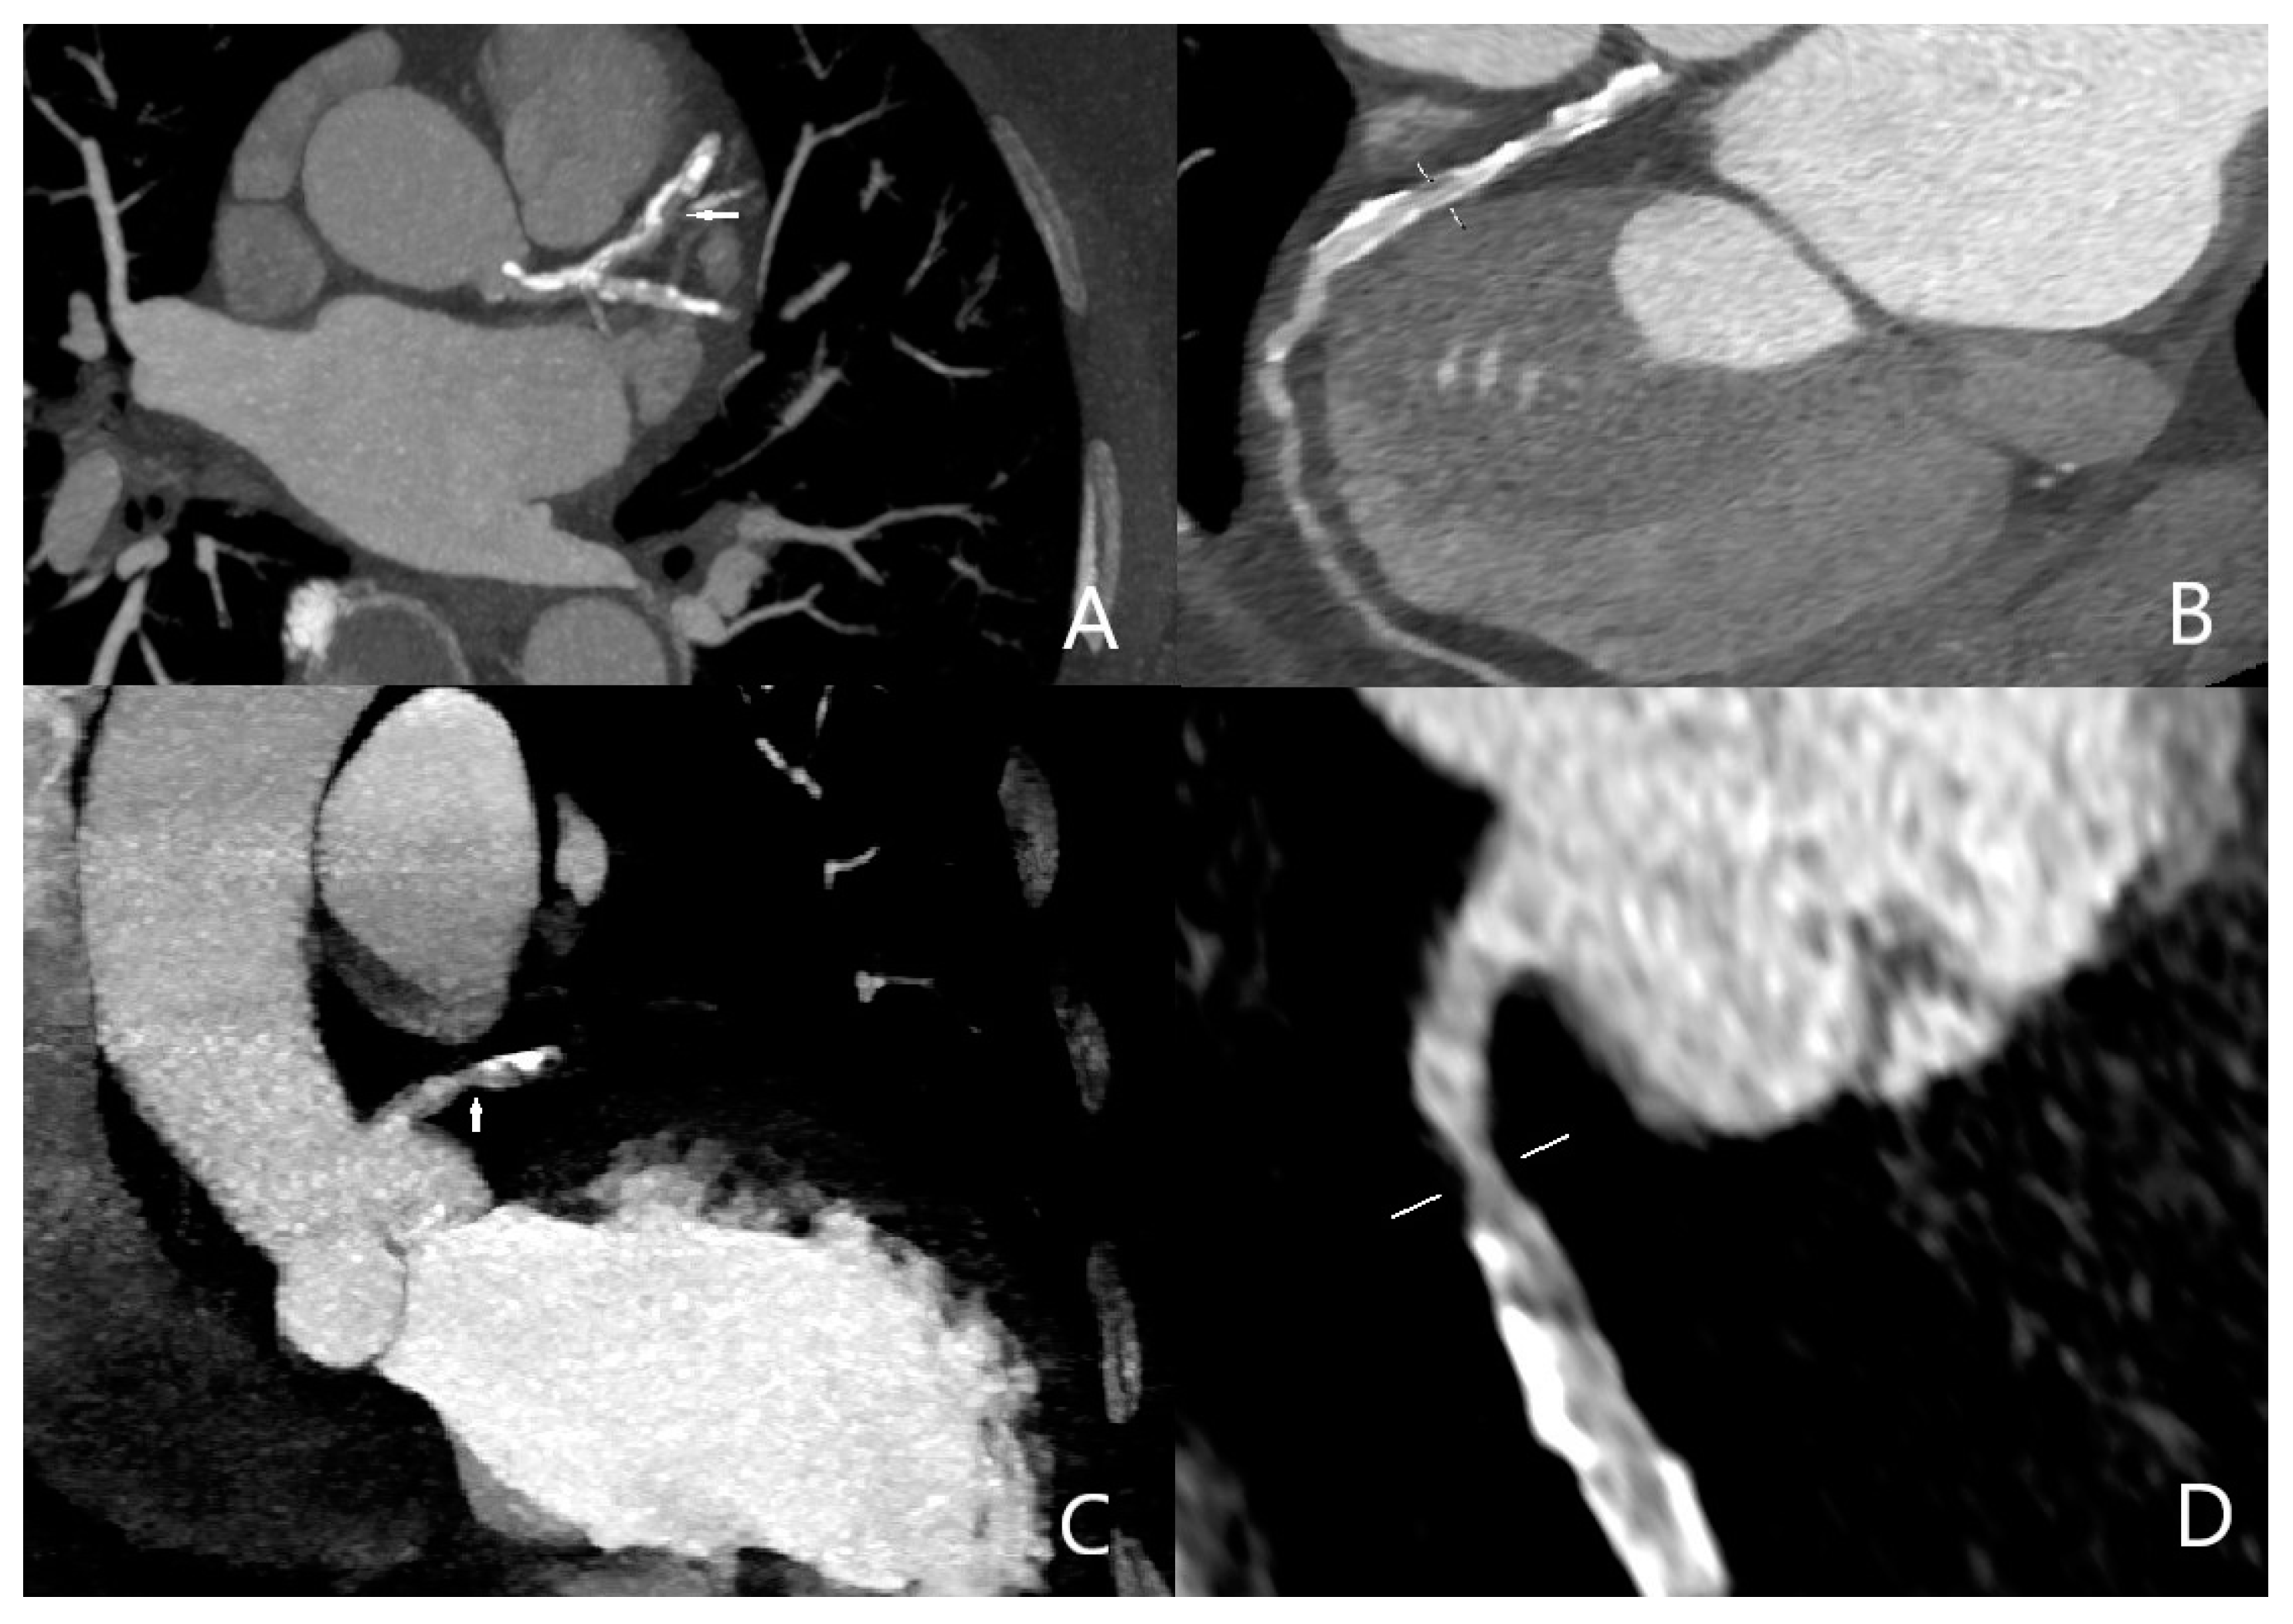

Three cases were overestimated as having obstructive coronary artery disease, and one case was underestimated as having negative obstructive coronary artery disease; all of the erroneous results were caused by calcified aterosclerotic plaques. Sensitivity, specificity, and positive and negative predictive values of quadruple-rule-out CT for obstructive coronary artery disease were 96.1% (95% confidence interval [CI] 93–99%), 93.4% (95%CI 90–99%), 89.2% (95%CI 86–94%), and 97.7% (95%CI 94–100%), respectively (Figure 2). Cohen’s coefficient of variation (ĸ value) for the presence of obstructive CAD was 0.78 (substantial).

Figure 2.

Obstructive coronary artery disease in the midportion of the left anterior descending artery ((A) arrow, (B) marking) and in the proximal portion of the right coronary artery ((C) arrow, (D) marking).